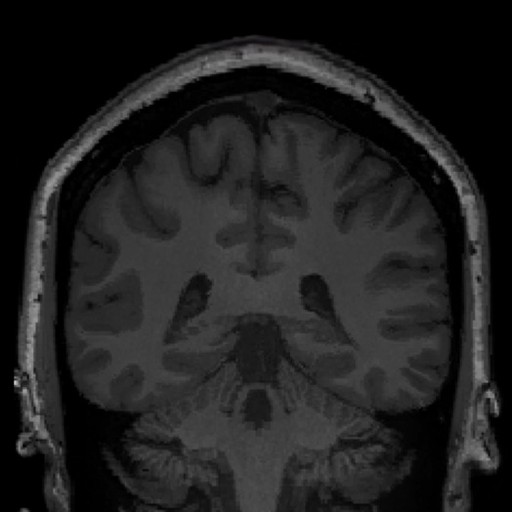

Analysis. Whole-brain morphometric mapping reveals deviation patterns across cortical and subcortical structures

Diagnostics. AI-powered lesion identification combined with expert radiologist validation delivers comprehensive case reports